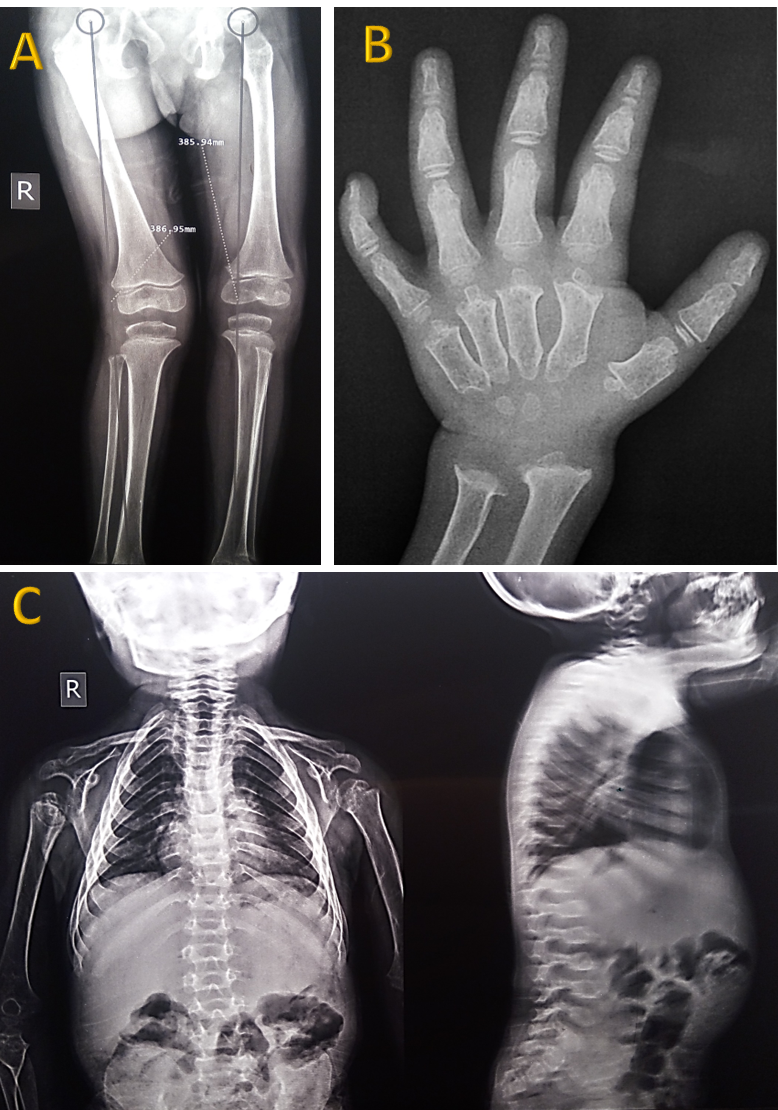

To date, the number of identified mutations in this disease continues to increase. We aim to introduce a novel missense point mutation in the GALNS gene that is associated with a severe form of MPS IVA. This mutation was detected in a three-year-old girl, born of consanguineous parents, who presented with genu valgus, pectus carinatum, cupping of the wrists, ulnar deviation of the radius and ulna, and kyphoscoliosis (Figure 1). The Berry spot test of the urine was positive for

Fig. 1. Skeletal abnormalities in our case of mucopolysaccharidosis type IVA. X- ray examination shows genu valgus (A), metaphyseal dysplasia, proximal metacarpal beaking, ulnar deviation of radius and ulna (B) and kyphoscoliosis (C). |